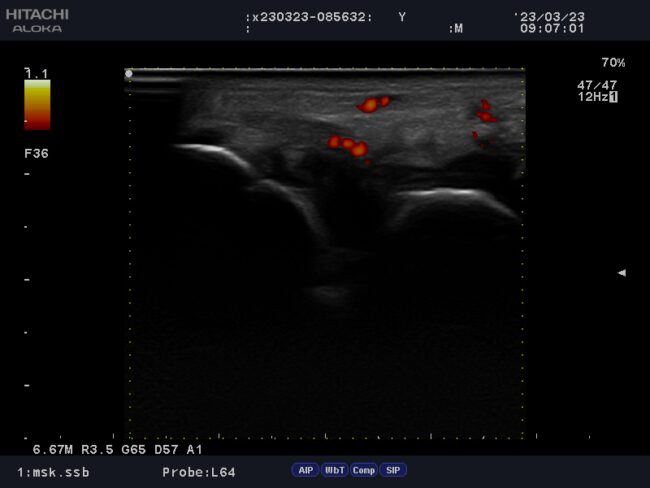

エコーとは人間の耳では聴こえない高い周波数の音波(超音波)を体表からプローブを介して発射し、体内の硬い組織(骨や臓器)で反射して戻ってきた音波を画像化する装置です。胎内の赤ちゃんの様子をみたり、健康診断で内臓を観察する際に用いられることが一般的ですが、骨折の有無や筋肉組織の状態(肉ばなれ)、靭帯損傷・関節部分の骨の変形、軟骨の摩耗具合等の評価にも用いられます。

当院では、このエコーを使用し患部の状態を観察する事で評価・治療効果の増大を図っています。